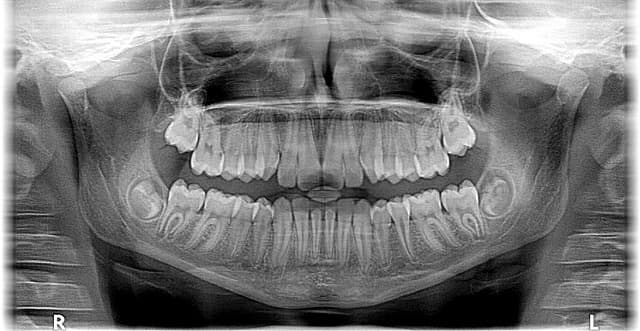

- 파노라마 엑스레이 및 CT 촬영: 치조골의 두께, 높이, 밀도를 평가하고 신경·혈관의 위치를 확인한다.